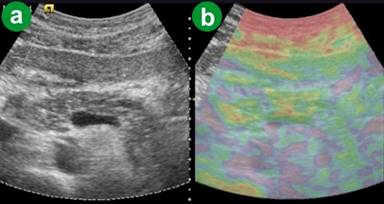

The Follow-up of Patients

The eSie touch images for parenchyma and peripancreatic fat for the five patients with ARFI-VTQ values greater than the upper detection limit were dark black (score 6) on gray scale and dark red (score 6) on color image at the time of the acute attack, or soon following the attack. The numerical expression of tissue hardness (i.e. the fall below the upper detection limit of 4.95 m/s) in these patients was possible from the 7th day following attack. The ARFI-VTQ values during the following days decreased gradually reaching the value of 2.2 m/s (i.e., the highest ARFI-VTQ value observed in the healthy control group) within about 4-6 weeks depending upon the intensity of infection. During this period, the eSie touch images turned from dark black (score 6) to gray (score 3) on the gray scale image and from dark red (score 6) to yellow (score 3) on the color scale. There were patchy areas of light gray color and blue-green color on the respective scales, indicating necrosis (Figure 6).

Figure 6. Acute resolving pancreatitis with necrosis and pseudocyst formation in the body. a. US B-mode image. b. eSie touch color scale image: patchy red parenchyma with focal green/purple area suggesting necrosis and pseudocyst formation. |